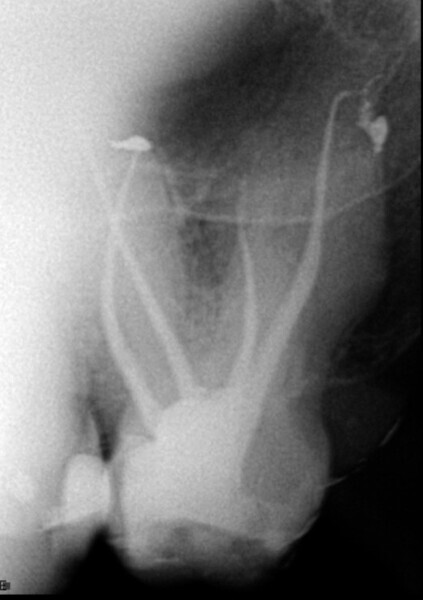

This patient attended in an emergency owing to sharp pain in a second maxillary molar. This was confirmed upon clinical examination. A standard radiograph was taken (Fig. 1), showing a very complex anatomy and calcified pulp chamber. The history of this tooth, as described by the patient, was that an inlay had been placed on it and discomfort developed after a while that had lasted several years untreated. On check-up, he had been told that everything was fine.

Fig. 1: Pre-op radiograph, showing a very complex root canal system and a calcified pulp chamber.